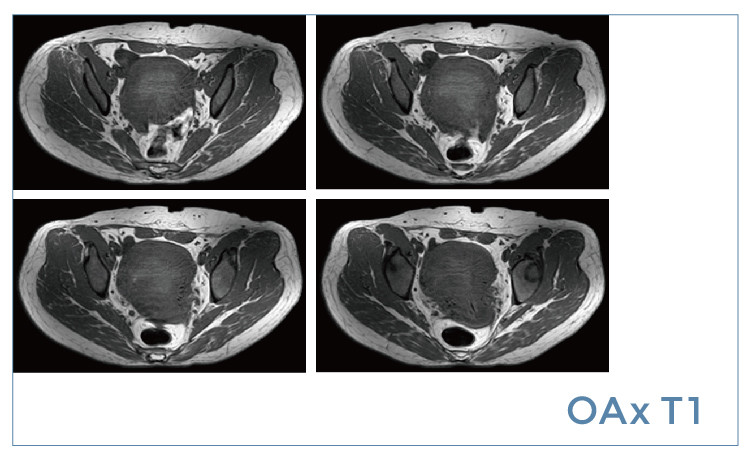

【朗润影像档案】磁共振影像病例分享(编号20190621)